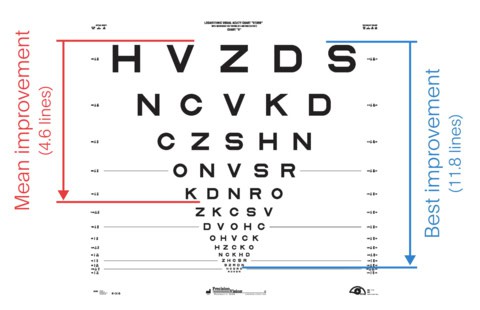

การทดลองดังกล่าวได้รับสมัครผู้เข้าร่วม 38 ราย โดยผู้เข้าร่วมการทดลองจะมีอายุ 60 ปีขึ้นไป มาจากในสหราชอาณาจักรและยุโรป แต่มีผู้เข้าร่วม 6 รายถอนตัวออกไปก่อนศึกษาครบ 1 ปี เพื่อวัดการพัฒนาด้านความคมชัดของการมองเห็น นักวิจัยใช้แผนภูมิสายตาแบบคลาสสิกในการวัด โดยอาสาสมัครเริ่มต้นด้วยความคมชัดของการมองเห็นโดยเฉลี่ยที่ 20/450 ขณะที่ความคมชัดของการมองเห็นปกติถือว่าอยู่ที่ 20/20 ซึ่งในสหรัฐอเมริกา สายตาที่จัดว่าบอดตามกฎหมายจะอยู่ที่ 20/200 หรือแย่กว่านั้น

หลังจากผ่านไป 1 ปี ผู้เข้าร่วมการทดลองจำนวน 32 คนสามารถอ่านแผนภูมิการมองเห็นได้เพิ่มขึ้นเกือบ 5 บรรทัด หรือ 23 ตัวอักษร เมื่อเทียบกับช่วงเริ่มต้นการศึกษา ซึ่งเพียงพอที่จะทำให้สายตาของพวกเขาดีขึ้นเป็น 20/160 โดยเฉลี่ย Daniel Palanker กล่าวว่า ผู้เข้าร่วมบางคนสามารถมองเห็นได้คมชัดถึง 20/63 โดยใช้คุณสมบัติซูมในตัวของอิมแพลนต์ แม้ว่าผู้เข้าร่วมส่วนใหญ่จะเห็นการปรับปรุงที่เห็นได้ชัดหลังจากผ่านไป 1 ปี แต่ผู้เข้าร่วม 5 คนไม่มีพัฒนาการด้านการมองเห็น ซึ่งนับว่าเป็นผลลัพธ์ที่ได้นั้นน่าประทับใจมาก